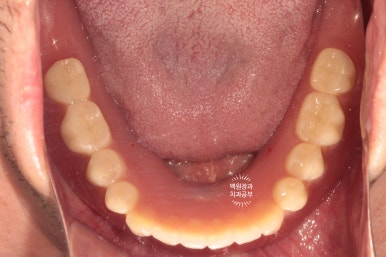

먼저 임플란트를 심어드린 아래턱 모습입니다.

두 개의 임플란트에 금색으로 된 모자를 연결해 주었어요.

이 부분이 나중에 임플란트와 연결할 단추 역할을 해줍니다.

이번에 새로 제작된 틀니입니다.

왼쪽이 위턱 오른쪽이 아래턱.. 잘 모르시겠죠?

왼쪽이 위턱, 오른쪽이 아래턱입니다.

눈치 빠르신 분은 아셨을텐데요, 아래턱 틀니의 치아가 없는 조직면을 보시면 구멍이 두개 뚫려있어요.

그 부분이 나중에 입 안에 튀어나와있는 금색 부분과 연결될 자리 !!

아래턱 틀니 안쪽면에 이렇게 까만색의 파트를 연결해주면,

입안에 틀니를 장착하실 때 딸깍딸깍 뺐다꼈다를 하실 수 있게 되어요.!!

이 녀석의 이름이 바로 오버덴쳐(overdenture)입니다. :)